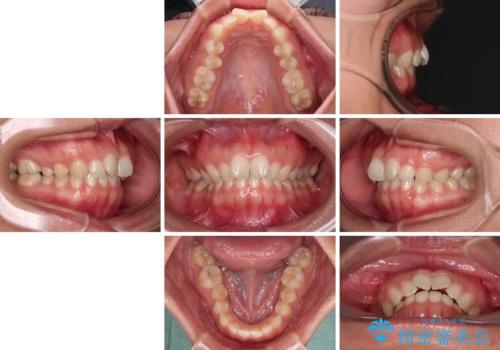

- 上の前歯が前方に飛び出していることを気にして来院された患者様です。

奥歯の咬み合わせをチェックすると、上顎歯列が相対的に前方に位置しているため、補助装置を用いて上顎歯列を確実に後方に移動させ、インビザラインで歯列を整えて行くこととしました。